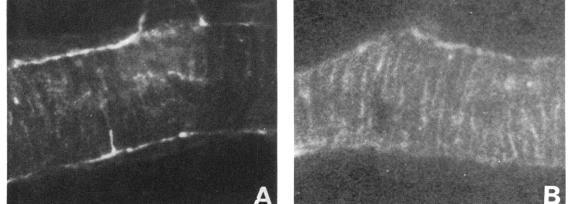

Reticulum fibres in relation to retinal vessels.

Argyrophilic perivascular and intervascular fibres in the mammalian retina are shown by specific antireticulin immunofluorescence to consist of reticulin. The possible significance of these findings is briefly discussed.